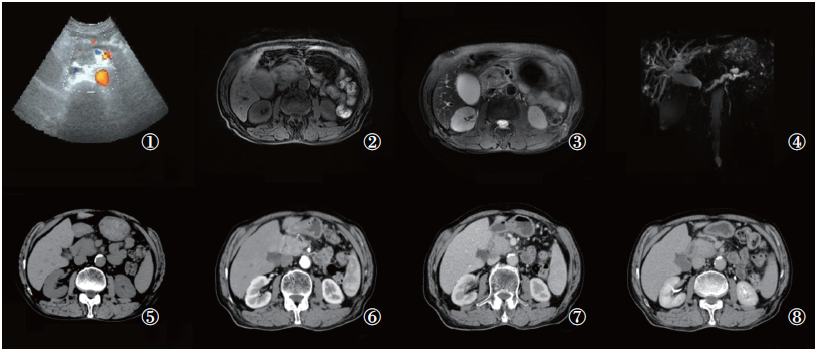

男性患者, 74岁, 因“ 发现胰腺肿物伴黄疸1月余” 入院。患者于2年前因上腹部疼痛在外院接受“ 胰腺炎” 治疗。出院后反复出现上腹部及剑突下疼痛, 行对症治疗效果不佳。1个月前再次出现上腹部疼痛, 在外院行对症治疗无好转, 症状逐渐加重遂来我院求诊, 我院门诊行上腹部CT检查提示胰腺肿物, 胆总管扩张。遂以“ 胰腺占位伴胆总管扩张” 收入外科, 拟行“ 胰腺肿瘤” 外科手术治疗。入院查血浆CA12-5、CA19-9、AFP、CEA值均正常。血浆D-二聚体升高(308 ng/mL), 血淀粉酶升高(283.5U/L), 黄疸指数(+)。彩超检查提示:胆囊肿大伴胆汁淤积, 肝内胆管及胰管扩张, 胰头区异常回声(占位性病变待排)(图1 ①)。MRI平扫显示:胰头区见结节状肿块, T1WI信号稍减低, T2WI信号稍减低(图1 ②~③); 磁共振胰胆管造影(magnetic resonance cholangio pancreatography, MRCP)提示胰头部肿块, 肿瘤性病变可能; 胰管、胆总管及肝内胆管扩张, 胆总管胰头部截断, 胆囊增大(图1 ④)。上腹部CT增强检查:胰头区见小片状稍低密度影, 边界不清, 动脉期病灶边缘强化, 静脉期及延迟期病灶逐渐呈充填式强化(图1 ⑤~⑧)。对上述各项影像学检查及生化指标进行综合分析, 初步诊断为胰头癌并梗阻性黄疸。故行经皮肝穿刺胆道引流术(percutaneous transhepatic cholangial drainage, PTCD)以缓解黄疸症状。鉴于目前缺乏病理学诊断依据, 对于胰腺癌的诊断尚缺乏最有力的证据, 决定行CT导向下胰腺穿刺活检术。活检细胞学HE染色显示:镜下见大量淋巴细胞及部分坏死细胞, 可见少量增大裸核(图2 ①~②)。病理检查提示:镜下见胰腺小叶间纤维组织增生伴大量慢性炎性细胞浸润, 以淋巴细胞、浆细胞为主, 小叶内少量慢性炎性细胞, 个别区域腺泡轻度增生, 未见其它特殊(图2 ③~④)。认为本例患者可疑诊断为IgG4-RAIP。

图2 胰腺标本活检细胞学、病理学及免疫组化检查

注: ①~②细胞学检查:镜下见大量淋巴细胞及部分坏死细胞, 可见大量增大的裸核; ③~④病理学HE染色:镜下见胰腺小叶间弥漫性纤维组织增生伴大量慢性炎性细胞浸润, 以淋巴细胞、浆细胞为主, 小叶内少量慢性炎性细胞浸润并个别区域腺泡轻度增生; ⑤~⑧病理学免疫组化:浆细胞CD38、CD138、IgG阳性, IgG4部分阳性, 其中IgG4> 10/HPF, 且IgG4/IgG> 40%; P53阴性

Fig.2 The cytology, immunohistochemistry and histochemistry examination of the biopsy specimens

Note: ①~② Cytology examination: A large number of lymphocytes and some necrotic cells are seen under the microscope, and a large number of enlarged naked nuclei are seen; ③~④ Histochemistry examination: Diffuse fibrous tissue hyperplasia between pancreatic lobules with a large number of chronic inflammatory cell infiltration, mainly lymphocytes and plasma cells, a small amount of chronic inflammatory cell infiltration in the lobules and mild acinar hyperplasia in some areas; ⑤~⑧ Immunohistochemistry: Plasma cells are positive for CD38, CD138, and IgG, and partly positive for IgG4, where IgG4> 10/HPF and IgG4/IgG> 40%; P53 negative

根据2011年国际胰腺病协会达成的共识, 对于可疑IgG4-RAIP患者, 病理学检查可以作为其诊断的“ 金标准” [2]。胰腺病灶靶向活检是鉴别胰腺癌与IgG4-RAIP必不可少的方法。我们通过Embase数据库检索到一项关于自身免疫性胰腺炎的组织病理学指南指出[12]:1型IgG4-RAIP病理学检查IgG4浆细胞数量明显增加, 通常每高倍镜视野> 50个; 而2型以粒细胞上皮病变为主要特征, 偶可见IgG4浆细胞, 且每高倍镜视野< 10个。在万方数据库中我们检索到一项对8例IgG4相关性疾病的临床和病理组织学研究指出[13], IgG4相关性疾病组织病理检查IgG4阳性的浆细胞每高倍镜视野为20~50个, 且IgG4/IgG> 40%。本例患者活检标本的免疫组化结果显示:浆细胞CD38、CD138、IgG阳性, IgG4部分阳性, 其中IgG4> 10/HPF, 且IgG4/IgG> 40%, Ki67低增殖(图2 ⑤~⑧)。查血清免疫球蛋白A及免疫球蛋白M均正常, 免疫球蛋白G升高(19.31 g/L), 抗核抗体(+)。血清IgG4检查结果为IgG4值13 g/L。验证了IgG4-RAIP诊断。回顾患者近两年来反复出现上腹部疼痛, 结合各项影像学检查、生化指标以及病理学检查结果, 可明确诊断为IgG4-RAIP, 硬化性胆管炎[2, 3, 4, 5, 6, 7, 8, 9, 10, 11, 12, 13, 14]。随后我们进一步在各大数据库中检索关于IgG4-RAIP治疗的证据。一项关于对IgG4-RAIP治疗的研究[15], 以及一项最新临床指南[16]均提示IgG4-RAIP治疗首选糖皮质激素, 并且疗效显著, 推荐起始治疗剂量为每日0.6 mg/kg, 2~4周后逐渐减量, 以2.5~5.0 mg/d的维持剂量治疗半年。遂给予本例患者口服泼尼松治疗, 起始剂量为40 mg/d。